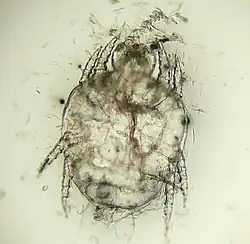

Le diagnostic repose sur l'observation de parasites, qu'ils soient adulte ou au stade d'oeufs[1].

Ils sont récupérés sur l'animal grâce à un râclage cutané superficiel, à un prélèvement à la bande adhésive, ou au ramassage de squames après un brossage, puis identifiés au microscope optique[1].